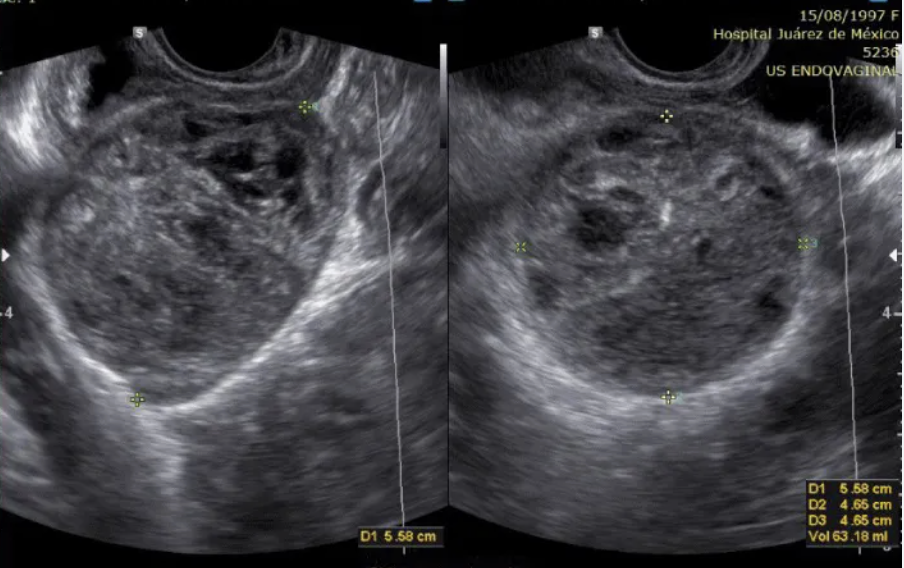

pt has amenorrhea + hirsutism. if the right ovary has the same appearance,

a) normal ovary w/multiple follicles

b) partial ovarian torsion

c) ovarian hyperstimulation

d) possible stein-leventhal syndrome